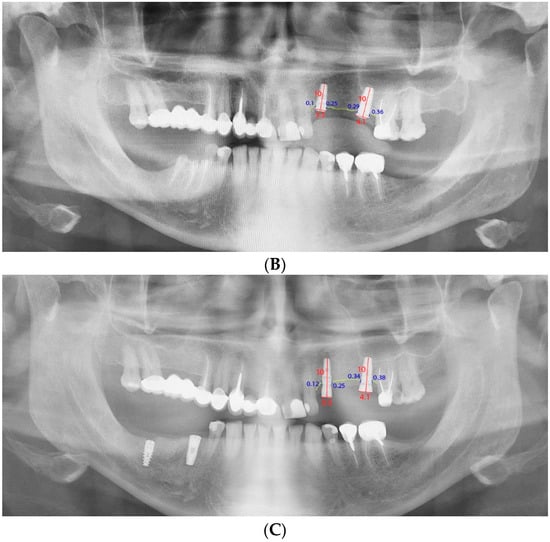

2.7. Radiographic Monitoring of Bone Loss

| Connection Type | T0–T1 | T1–T2 | T0–T2 | ||||||

|---|---|---|---|---|---|---|---|---|---|

| Mean | SD | 95% CI | Mean | SD | 95% CI | Mean | SD | 95% CI | |

| ICC | 0.17 | 0.28 | 0.1–0.24 | 0.19 | 0.17 | 0.15–0.24 | 0.36 | 0.34 | 0.3–0.45 |

| EC | 0.18 | 0.21 | 0.1–0.26 | 0.39 | 0.24 | 0.3–0.48 | 0.57 | 0.37 | 0.4–0.71 |

| t-test | −0.26 | – | – | −4.4 | – | – | −2.74 | – | – |

| p-value | 0.79 | – | – | 0.00 | – | – | 0.01 | – | – |